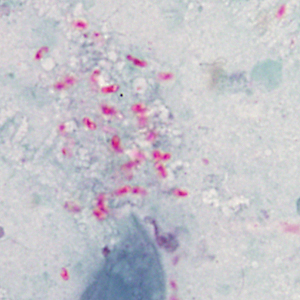

A 27-year-old HIV-positive male presented with abdominal pain and chronic diarrhea. He had a history of AIDS cholangiopathy. Recent microbiology results included bacteremia caused by Enterobacter species and sputum cultures positive for Mycobacterium avium-complex (MAC). During routine examination of Gram-stained bronchial alveolar lavage (BAL) specimens, suspect objects were observed by the attending technologist. Additional BAL material was stained with calcofluor white and Gram chromotrope, and the suspect objects were observed being positive for both. Images were captured of the BAL stained with Gram chromotrope (Figures A and B) and sent to the DPDx Team for diagnostic assistance. Additionally, the BAL specimen was forwarded on to the DPDx Team for additional work-up. The DPDx Team prepared a fresh smear from the BAL, stained with chromotrope 2R, and observed similar objects at 1000x with oil (Figures C and D), which measured approximately 2.0 micrometers in length. What is your diagnosis? Based on what criteria? What additional tests, if any, would you recommend?

Figure A

Figure B